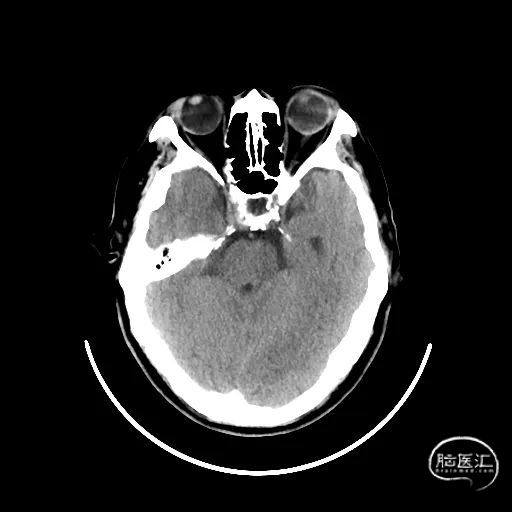

颅脑CT:未见明显缺血/出血病灶。

CTA提示:右侧椎动脉纤细,左侧椎动脉V1、V4段纤细。

MRI提示小脑缺血性改变。

术后CT:未见明显脑出血,双侧小脑低密度影。